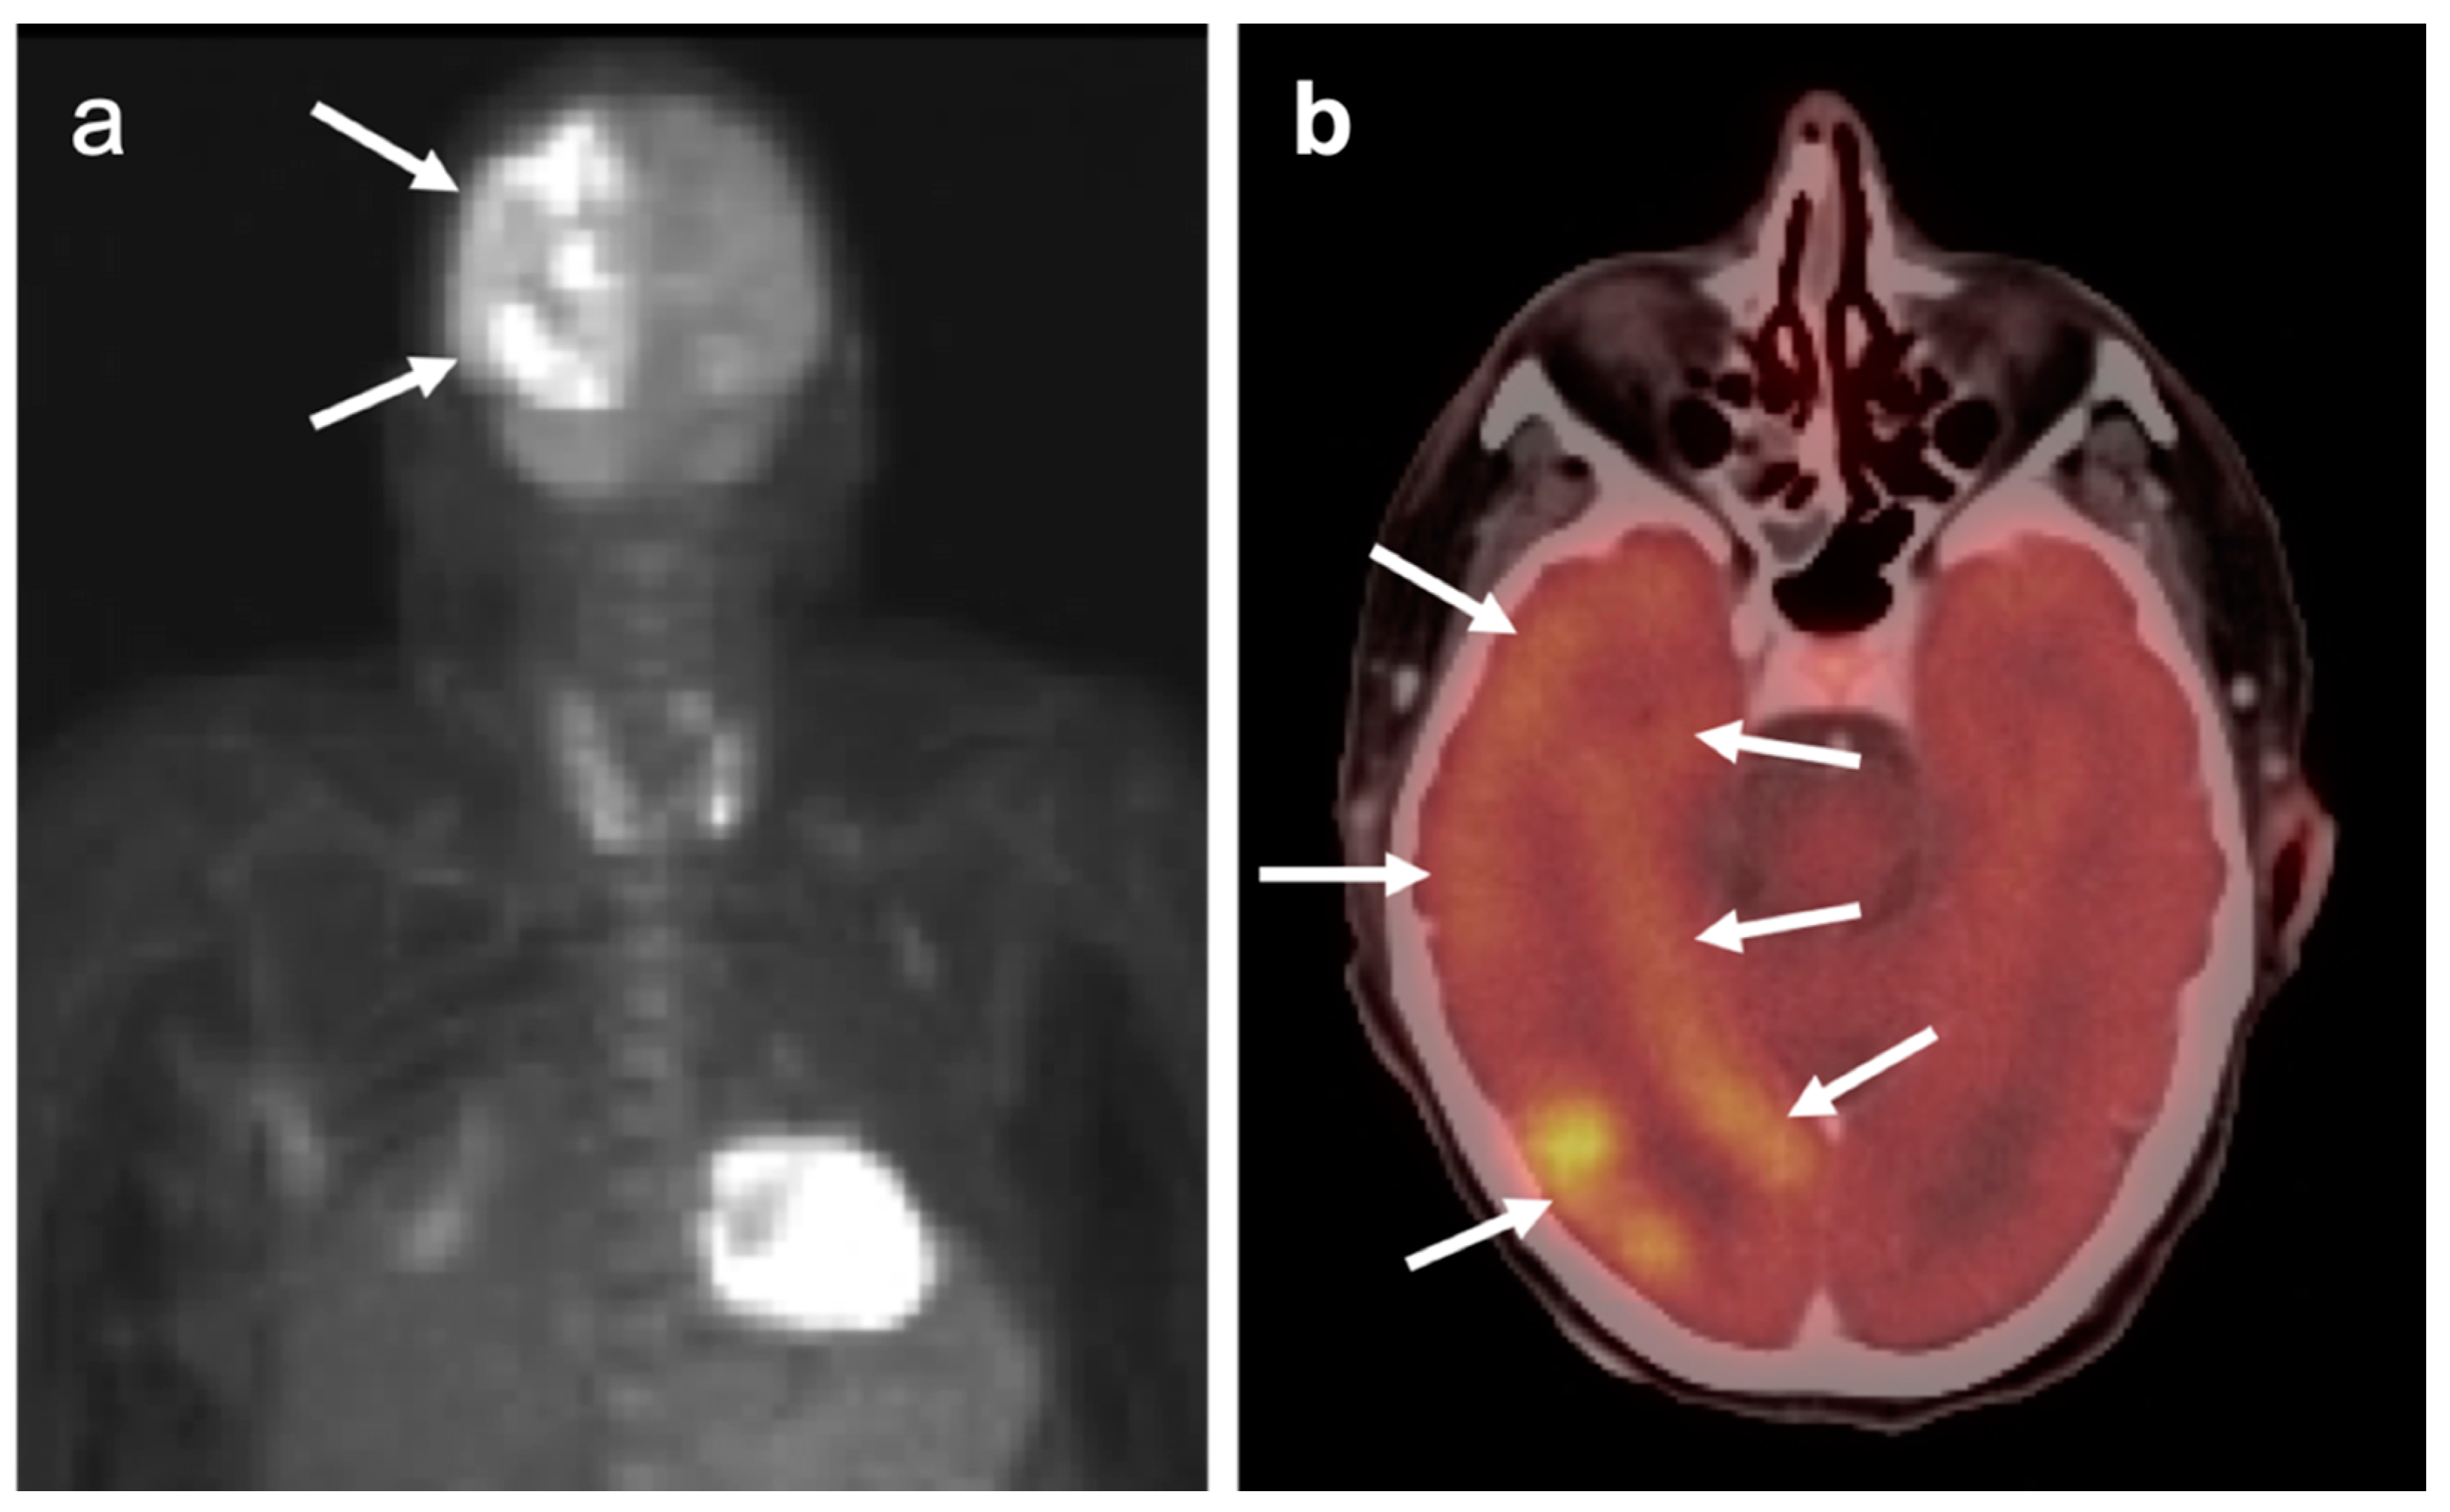

3.4. CNS Lymphoma

3.5. Brain Metastases